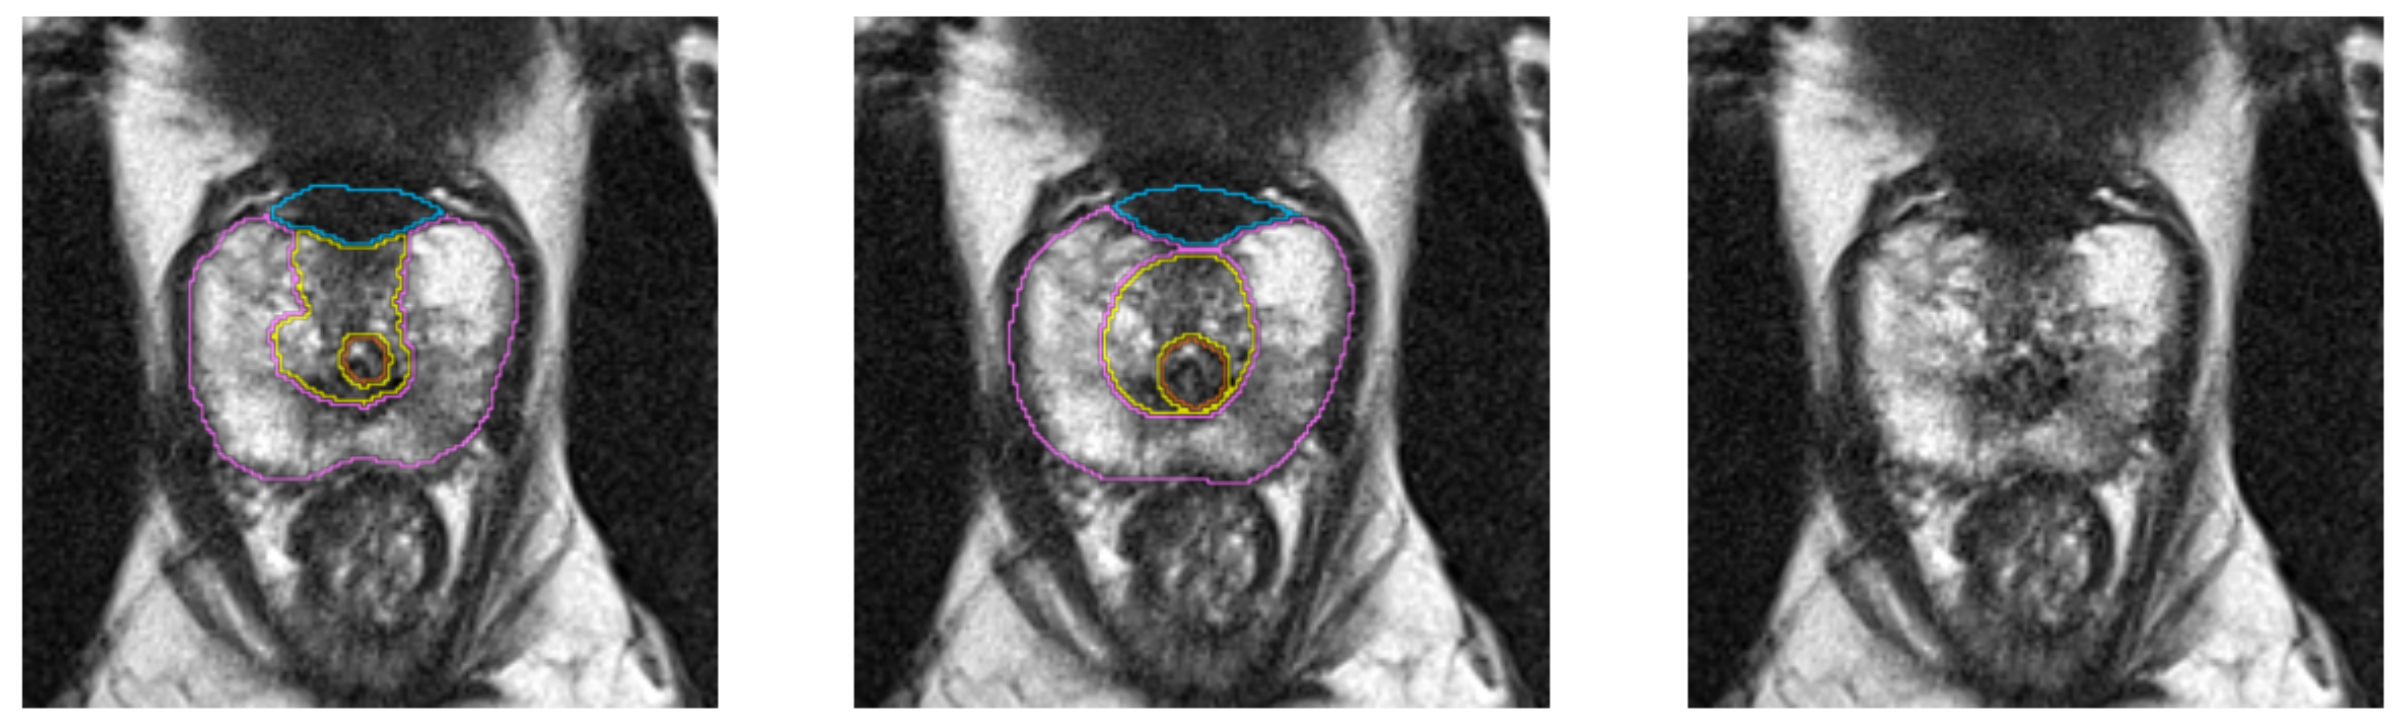

Segmentation Example 3